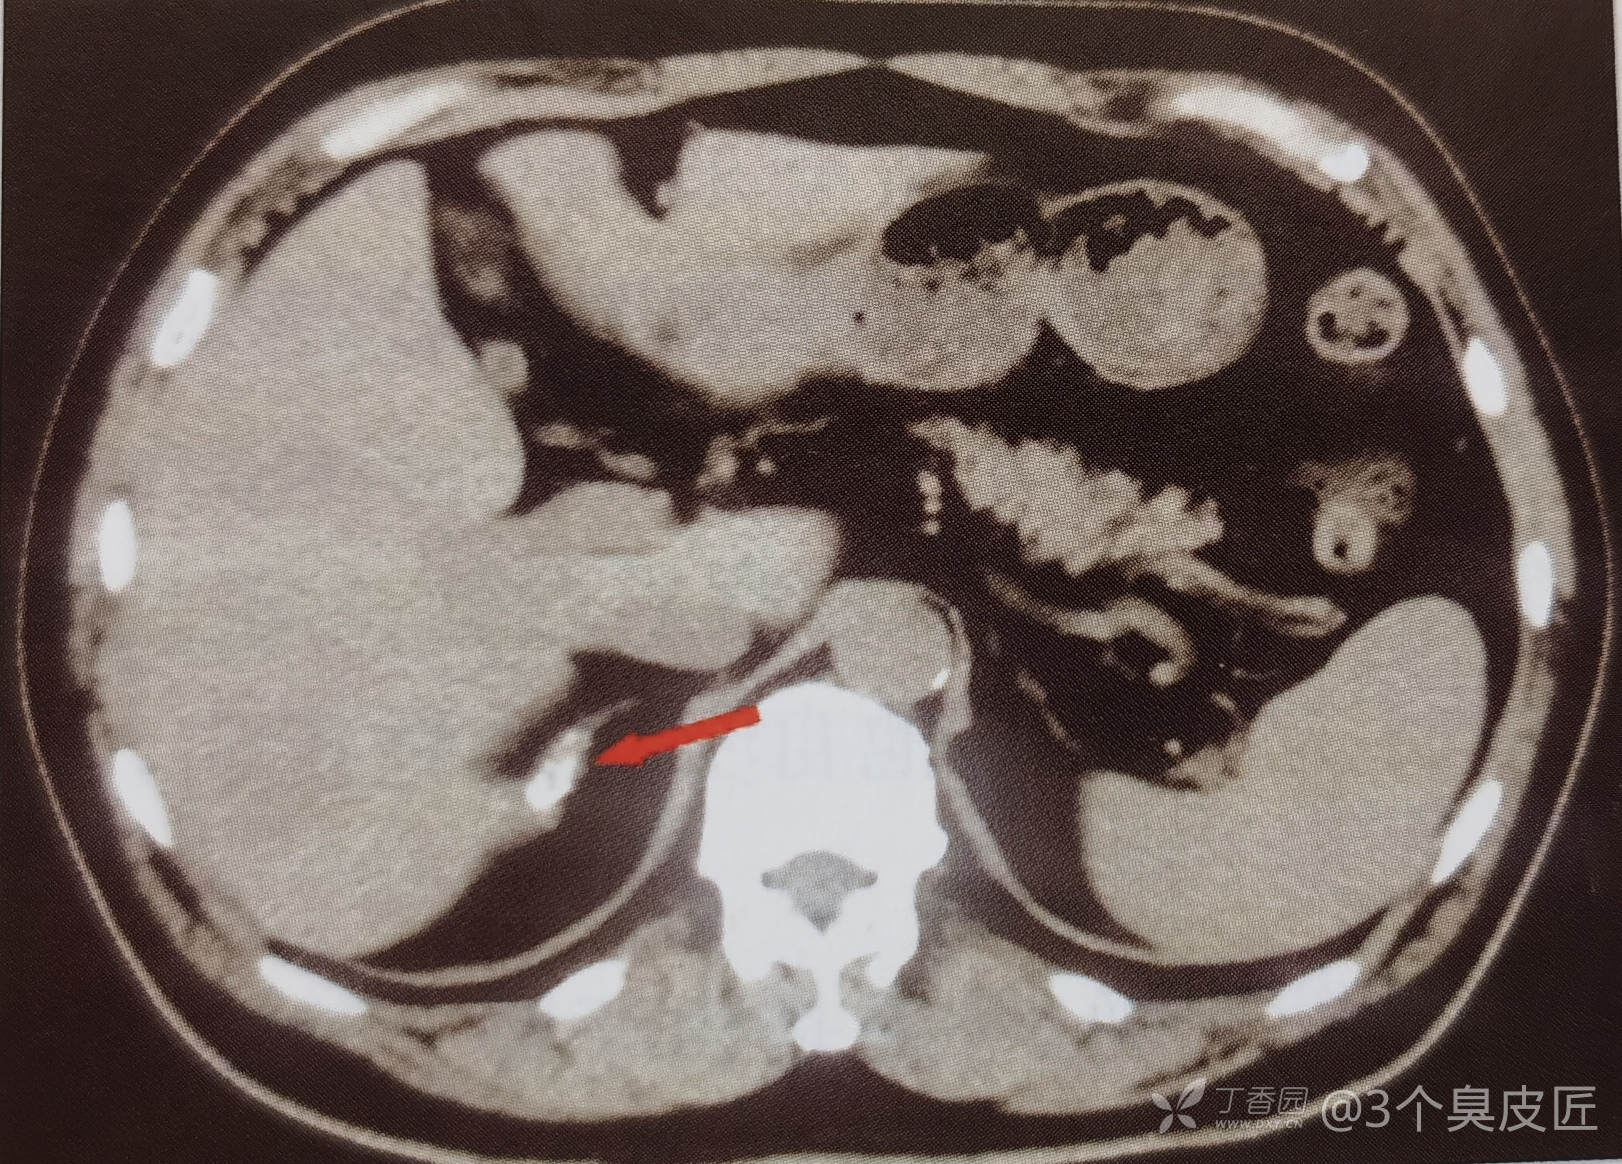

肾上腺CT:右侧肾上腺钙化,提示其为原发性肾上腺皮质功能减退的病因。